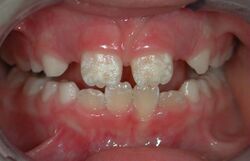

Irreversible enamel defects caused by an untreated celiac disease. They may be the only clue to its diagnosis, even in absence of gastrointestinal symptoms, but are often confused with fluorosis, tetracycline discoloration, or other causes.[48][49][50] The National Institutes of Health include a dental exam in the diagnostic protocol of celiac disease.[48]

There are 14 different types of amelogenesis imperfecta.[3] The hypocalcification type, which is the most common, is an autosomal dominant condition that results in enamel that is not completely mineralized.[51] Consequently, enamel easily flakes off the teeth, which appear yellow because of the revealed dentin. The hypoplastic type is X-linked and results in normal enamel that appears in too little quantity, having the same effect as the most common type.[51]